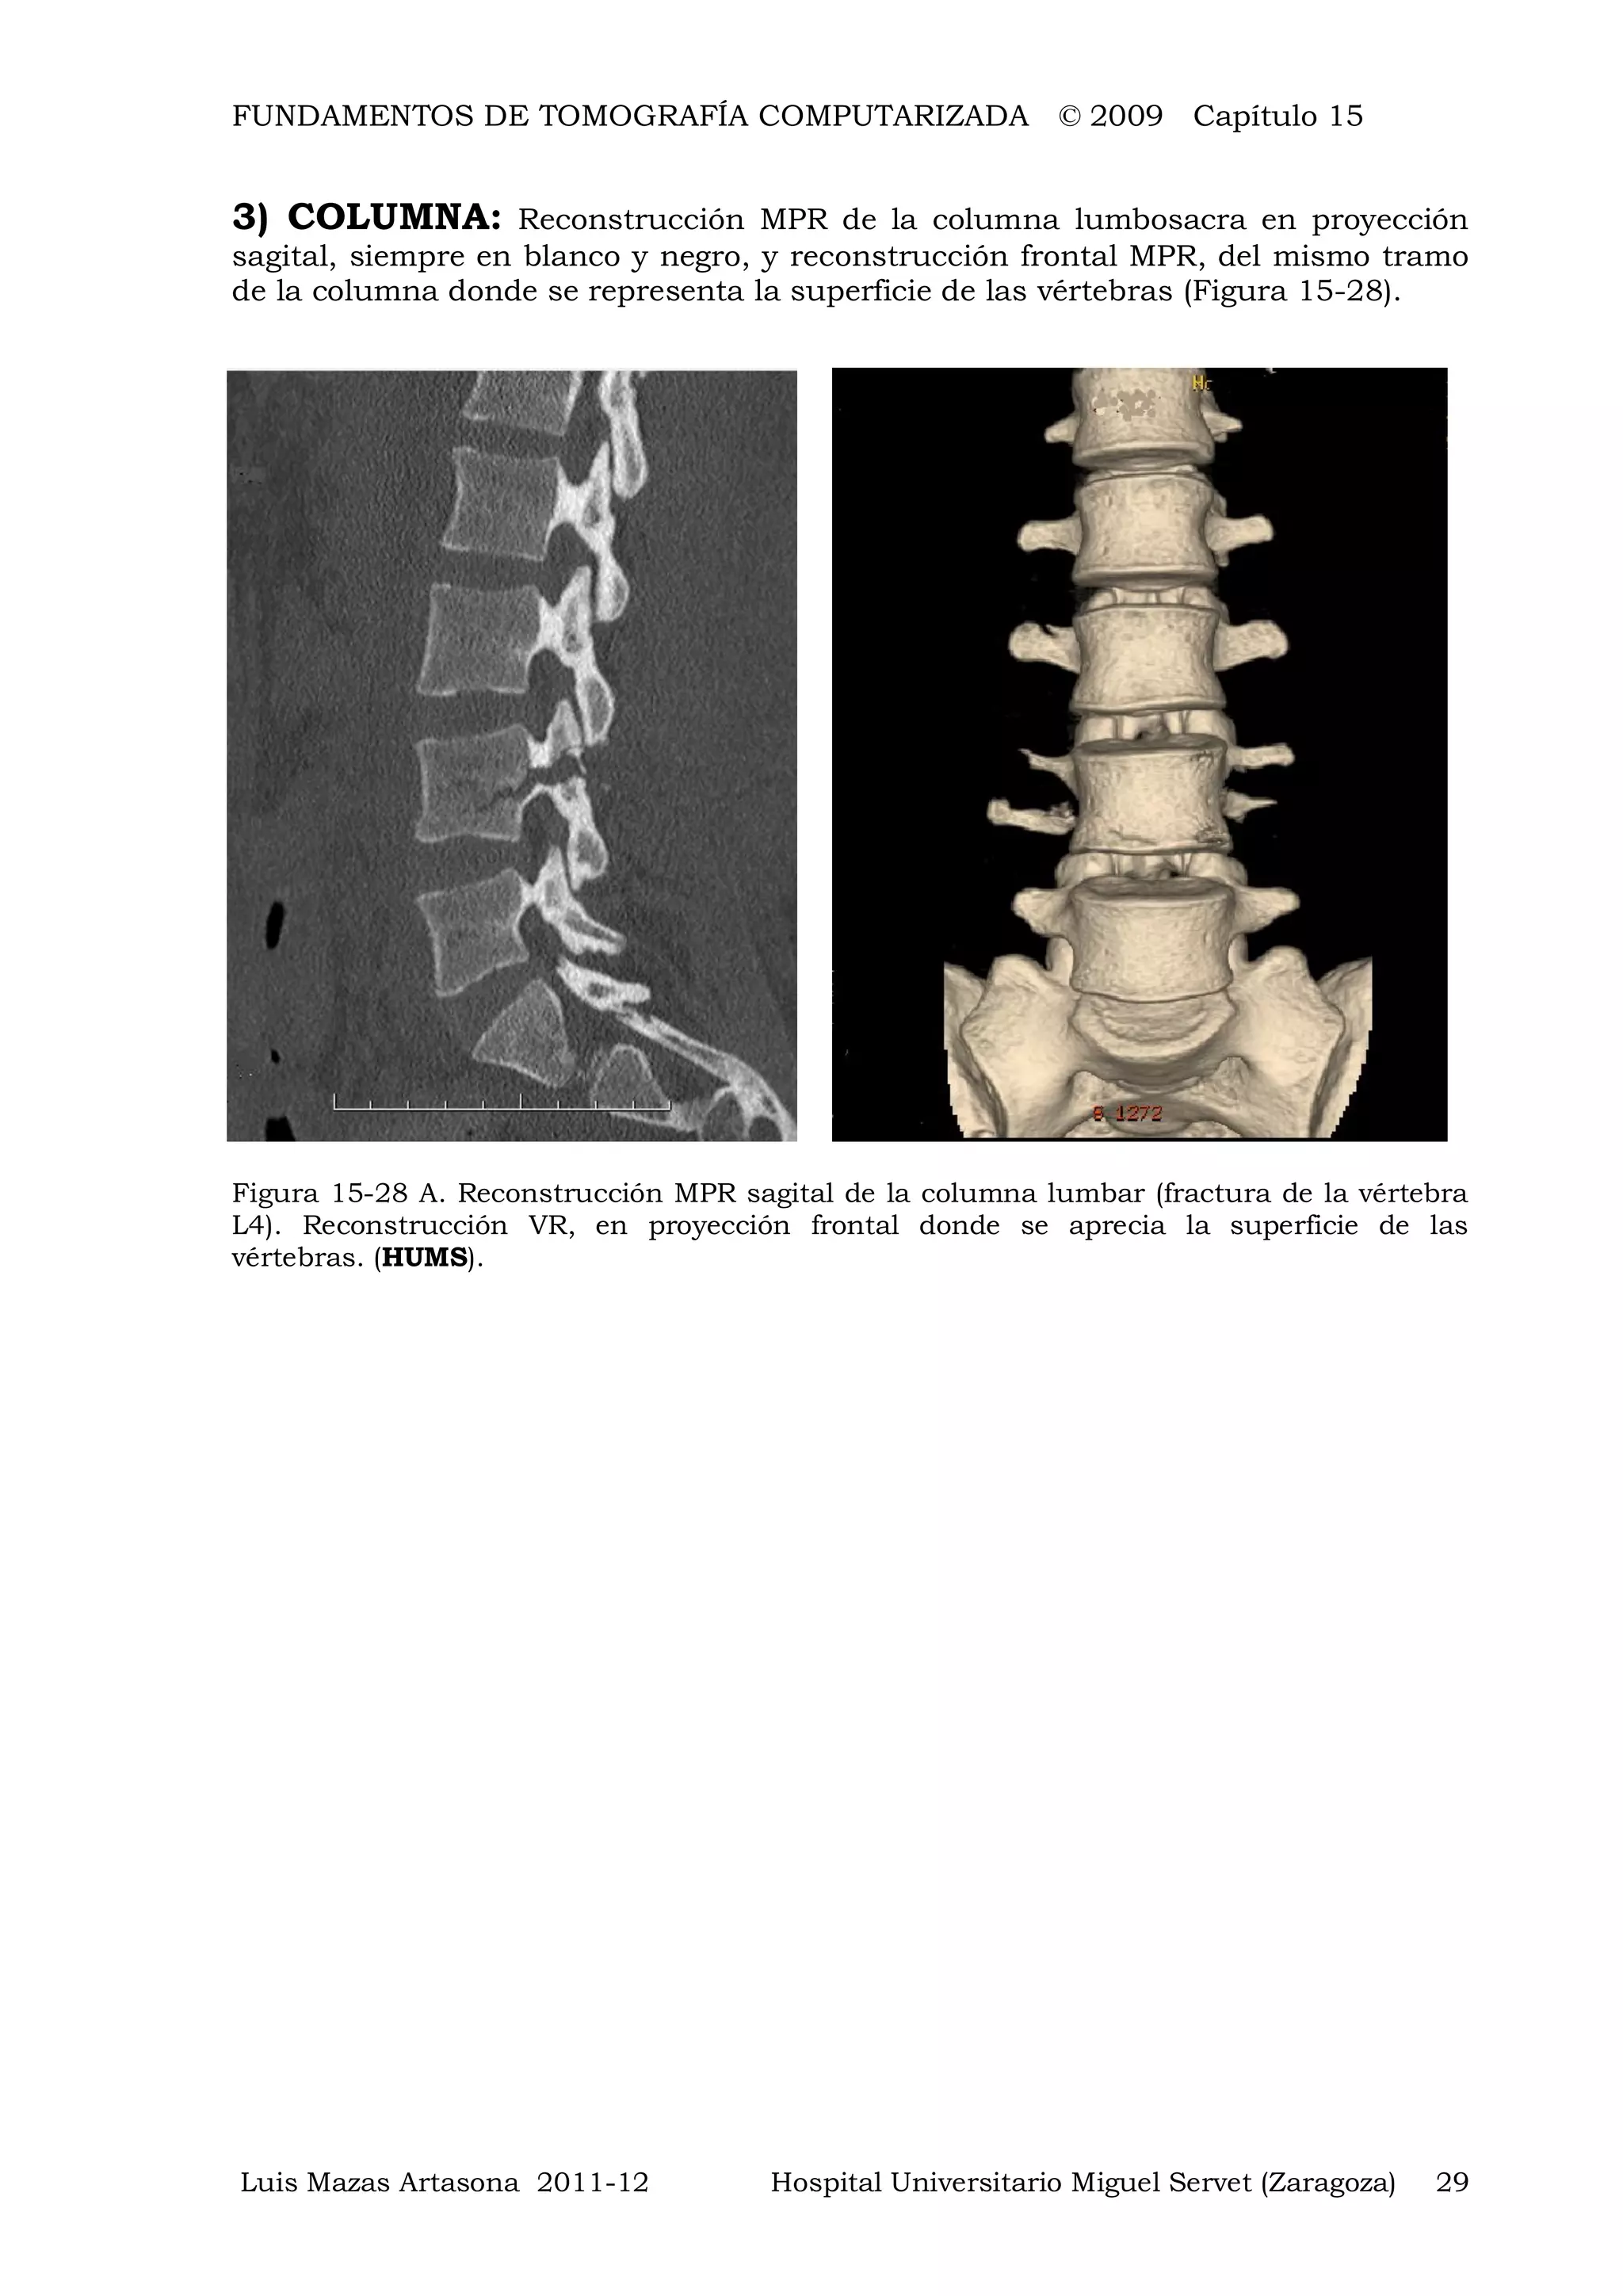

3) COLUMNA: Reconstrucción MPR de la columna lumbosacra en proyección

Figura 15-28 A. Reconstrucción MPR sagital de la columna lumbar (fractura de la vértebra

L4). Reconstrucción VR, en proyección frontal donde se aprecia la superficie de las

vértebras. (HUMS).